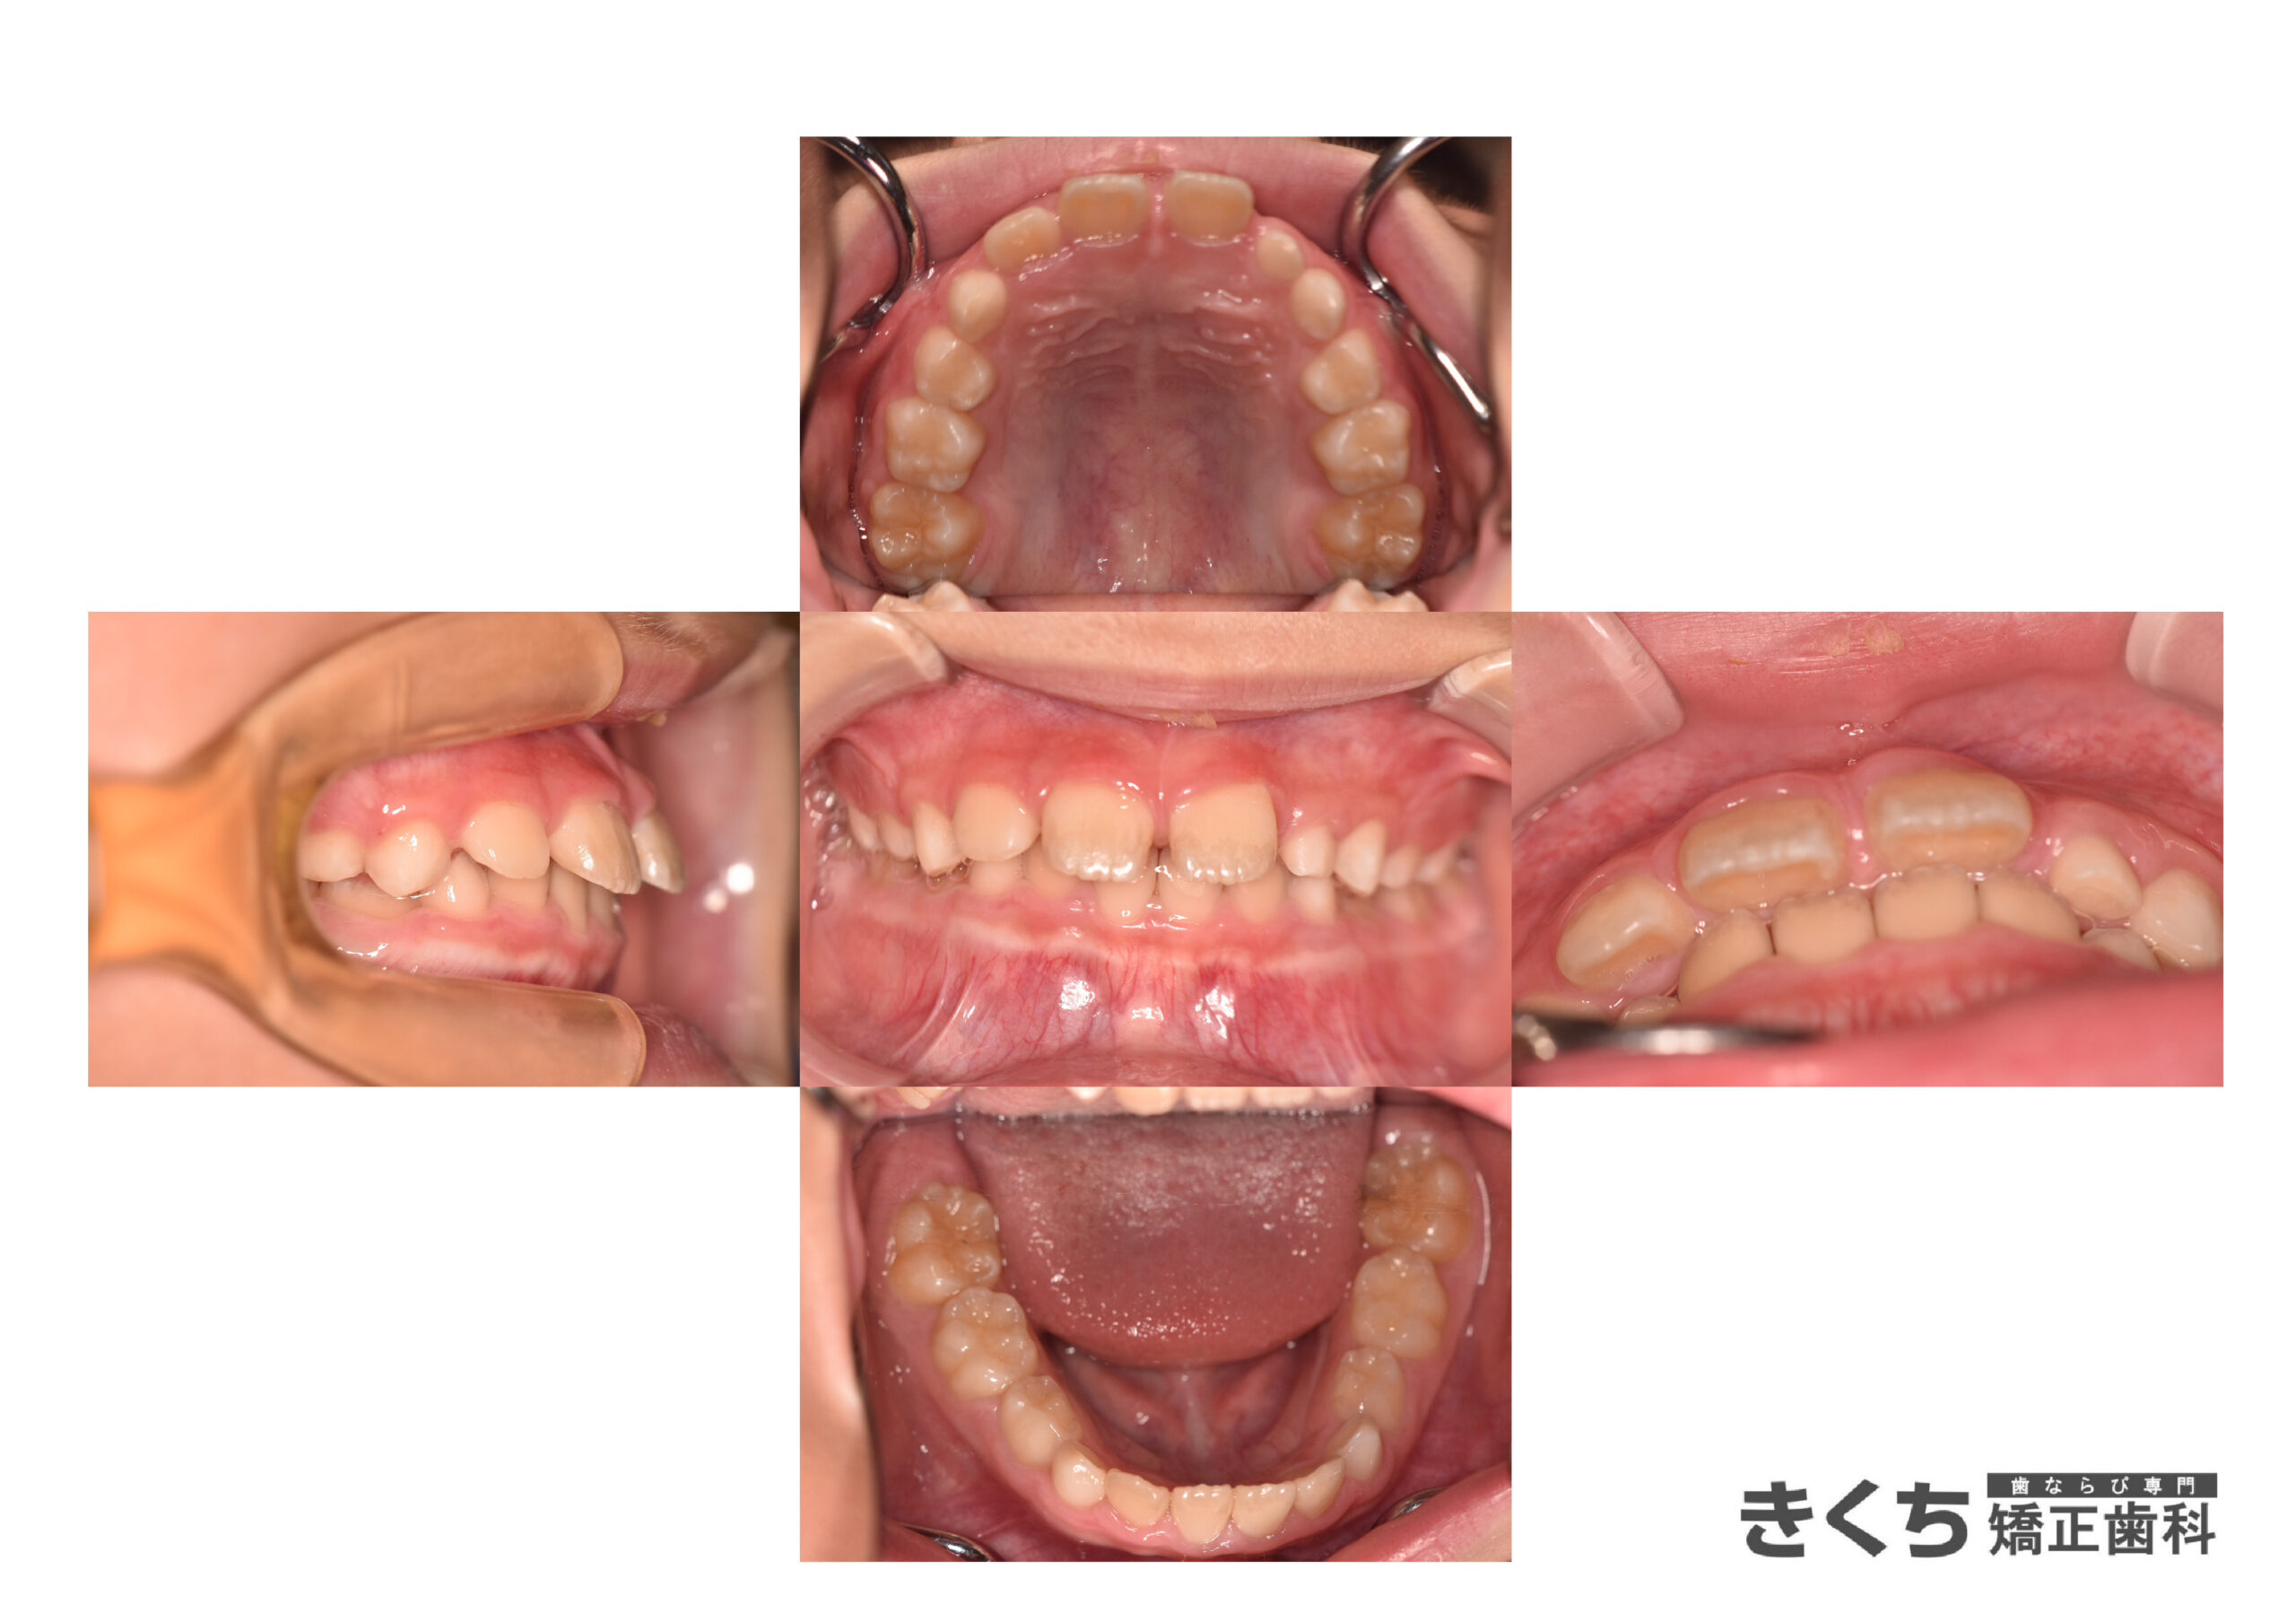

初診時8歳、上の前歯の隙間を気にして来院

他院にて今すぐ矯正治療を始めたほうがいいと指摘を受けた

→6ヶ月ごとのペースで経過観察

口腔筋機能を改善するために指導を行いました。

↓↓↓↓↓↓↓ 1年後

口腔筋機能 の改善だけで、上の前歯の隙間が自然に改善しました。